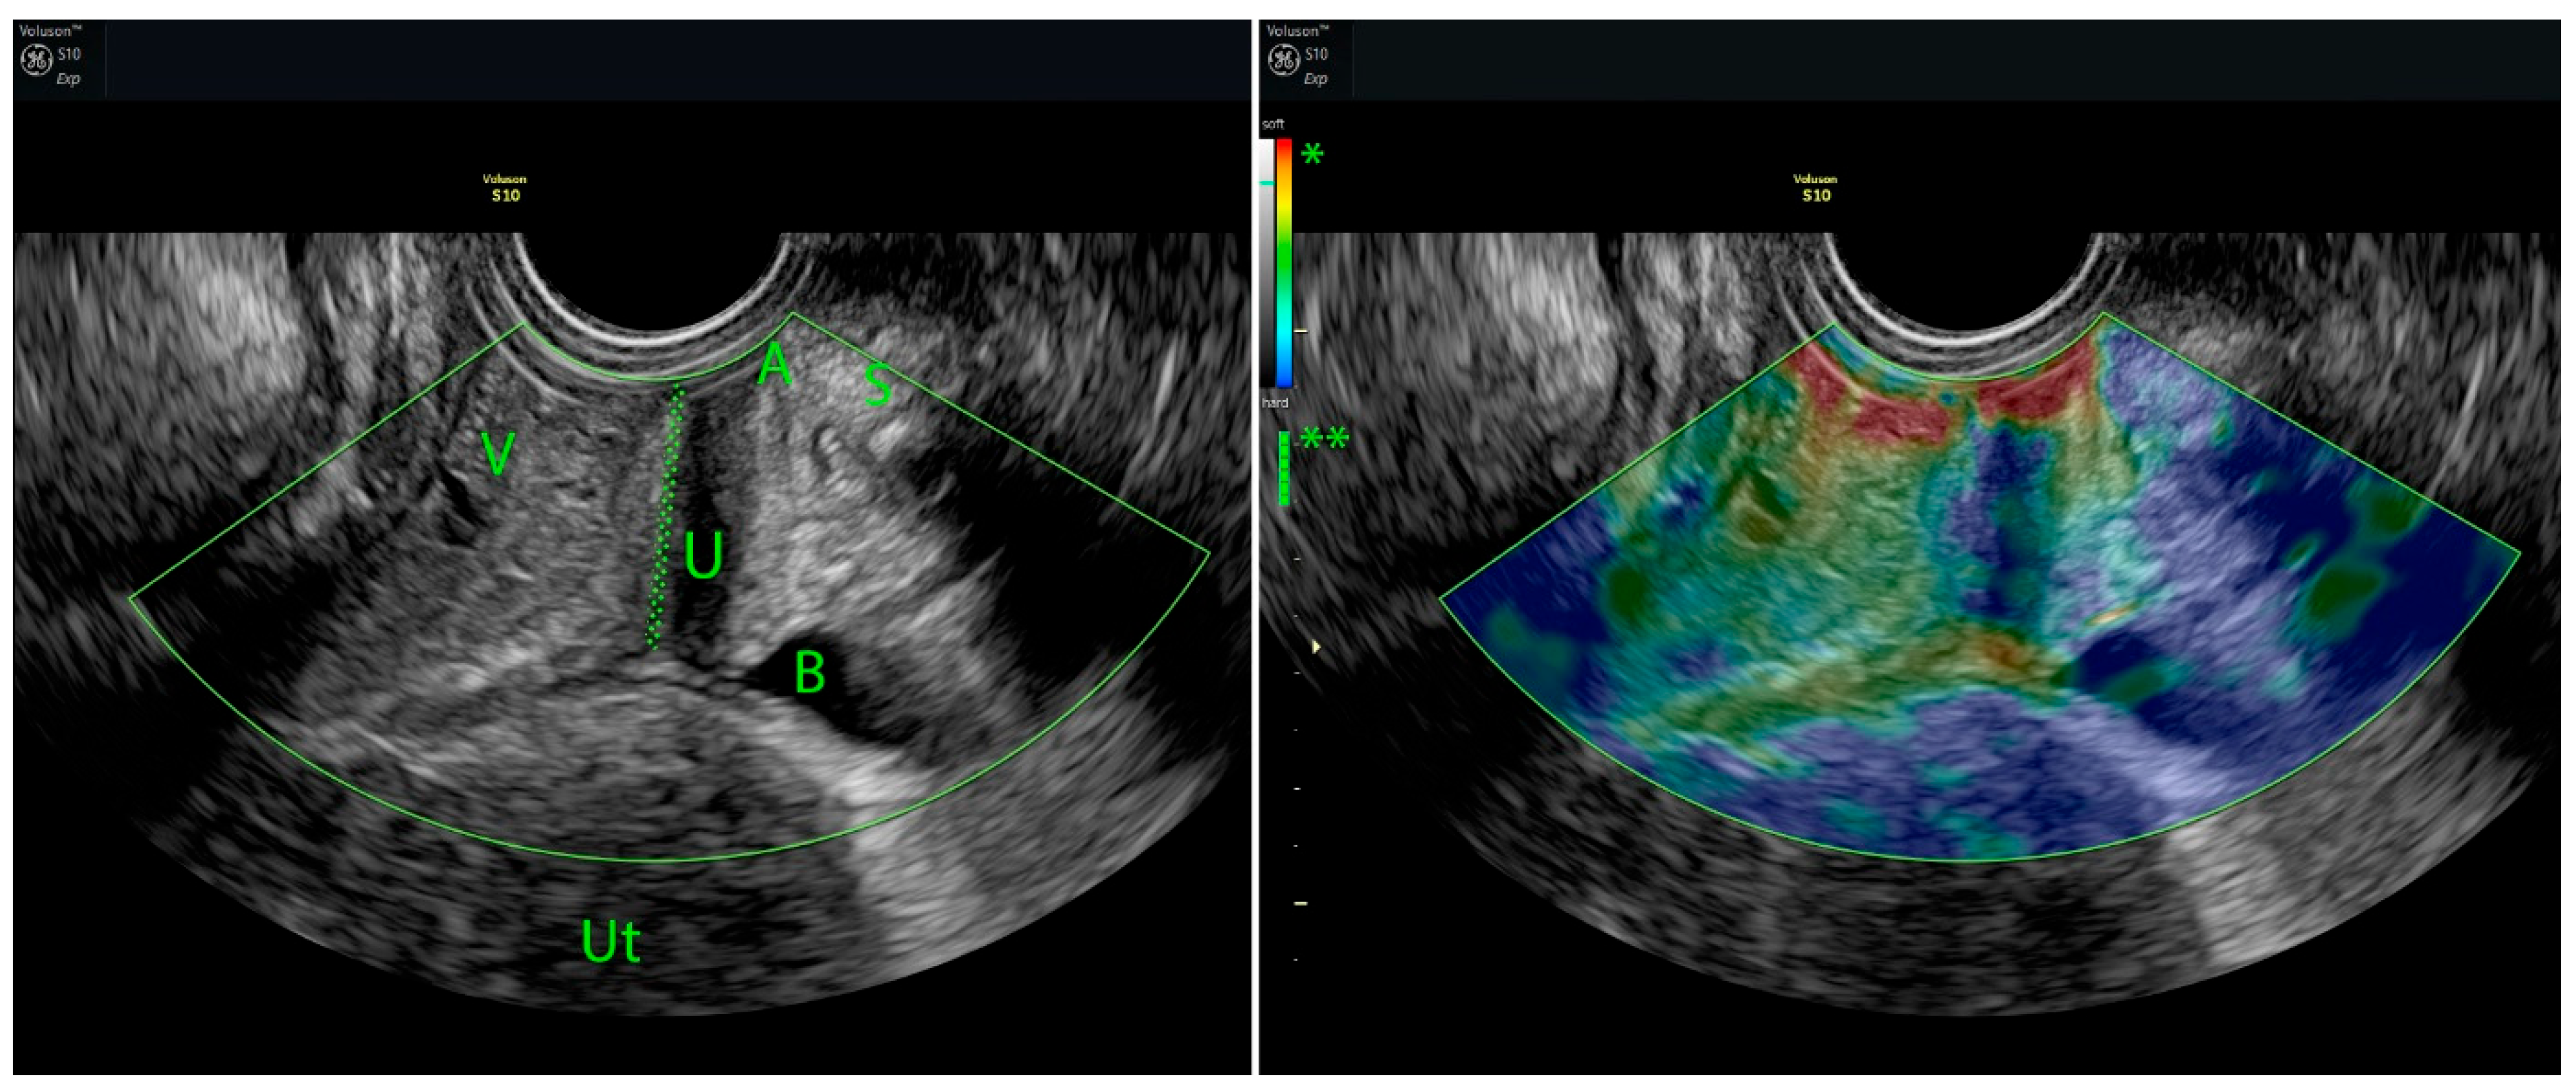

5.1. Strain Elastography (SE)

- Csákány, L.; Kozinszky, Z.; Kovács, F.; Krajczár, S.K.; Várbíró, S.; Keresztúri, A.; Németh, G.; Surányi, A.; Pásztor, N. Evaluation of Suburethral Tissue Elasticity Using Strain Elastography in Women with Stress Urinary Incontinence. J. Clin. Med. 2025, 14, 5617. [Google Scholar] [CrossRef]